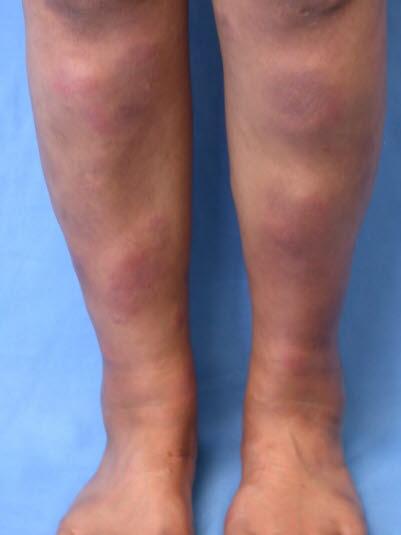

Erythema nodosum, knuterosen

Erythema nodosum (knuterosen) er en akutt betennelse (inflammasjon) i underhudsfettet (pannikulitt). Tilstanden viser seg i starten som en hevelse med røde knuter som er svært følsomme for trykk. De fleste knutene er lokalisert symmetrisk på forsiden av leggene.